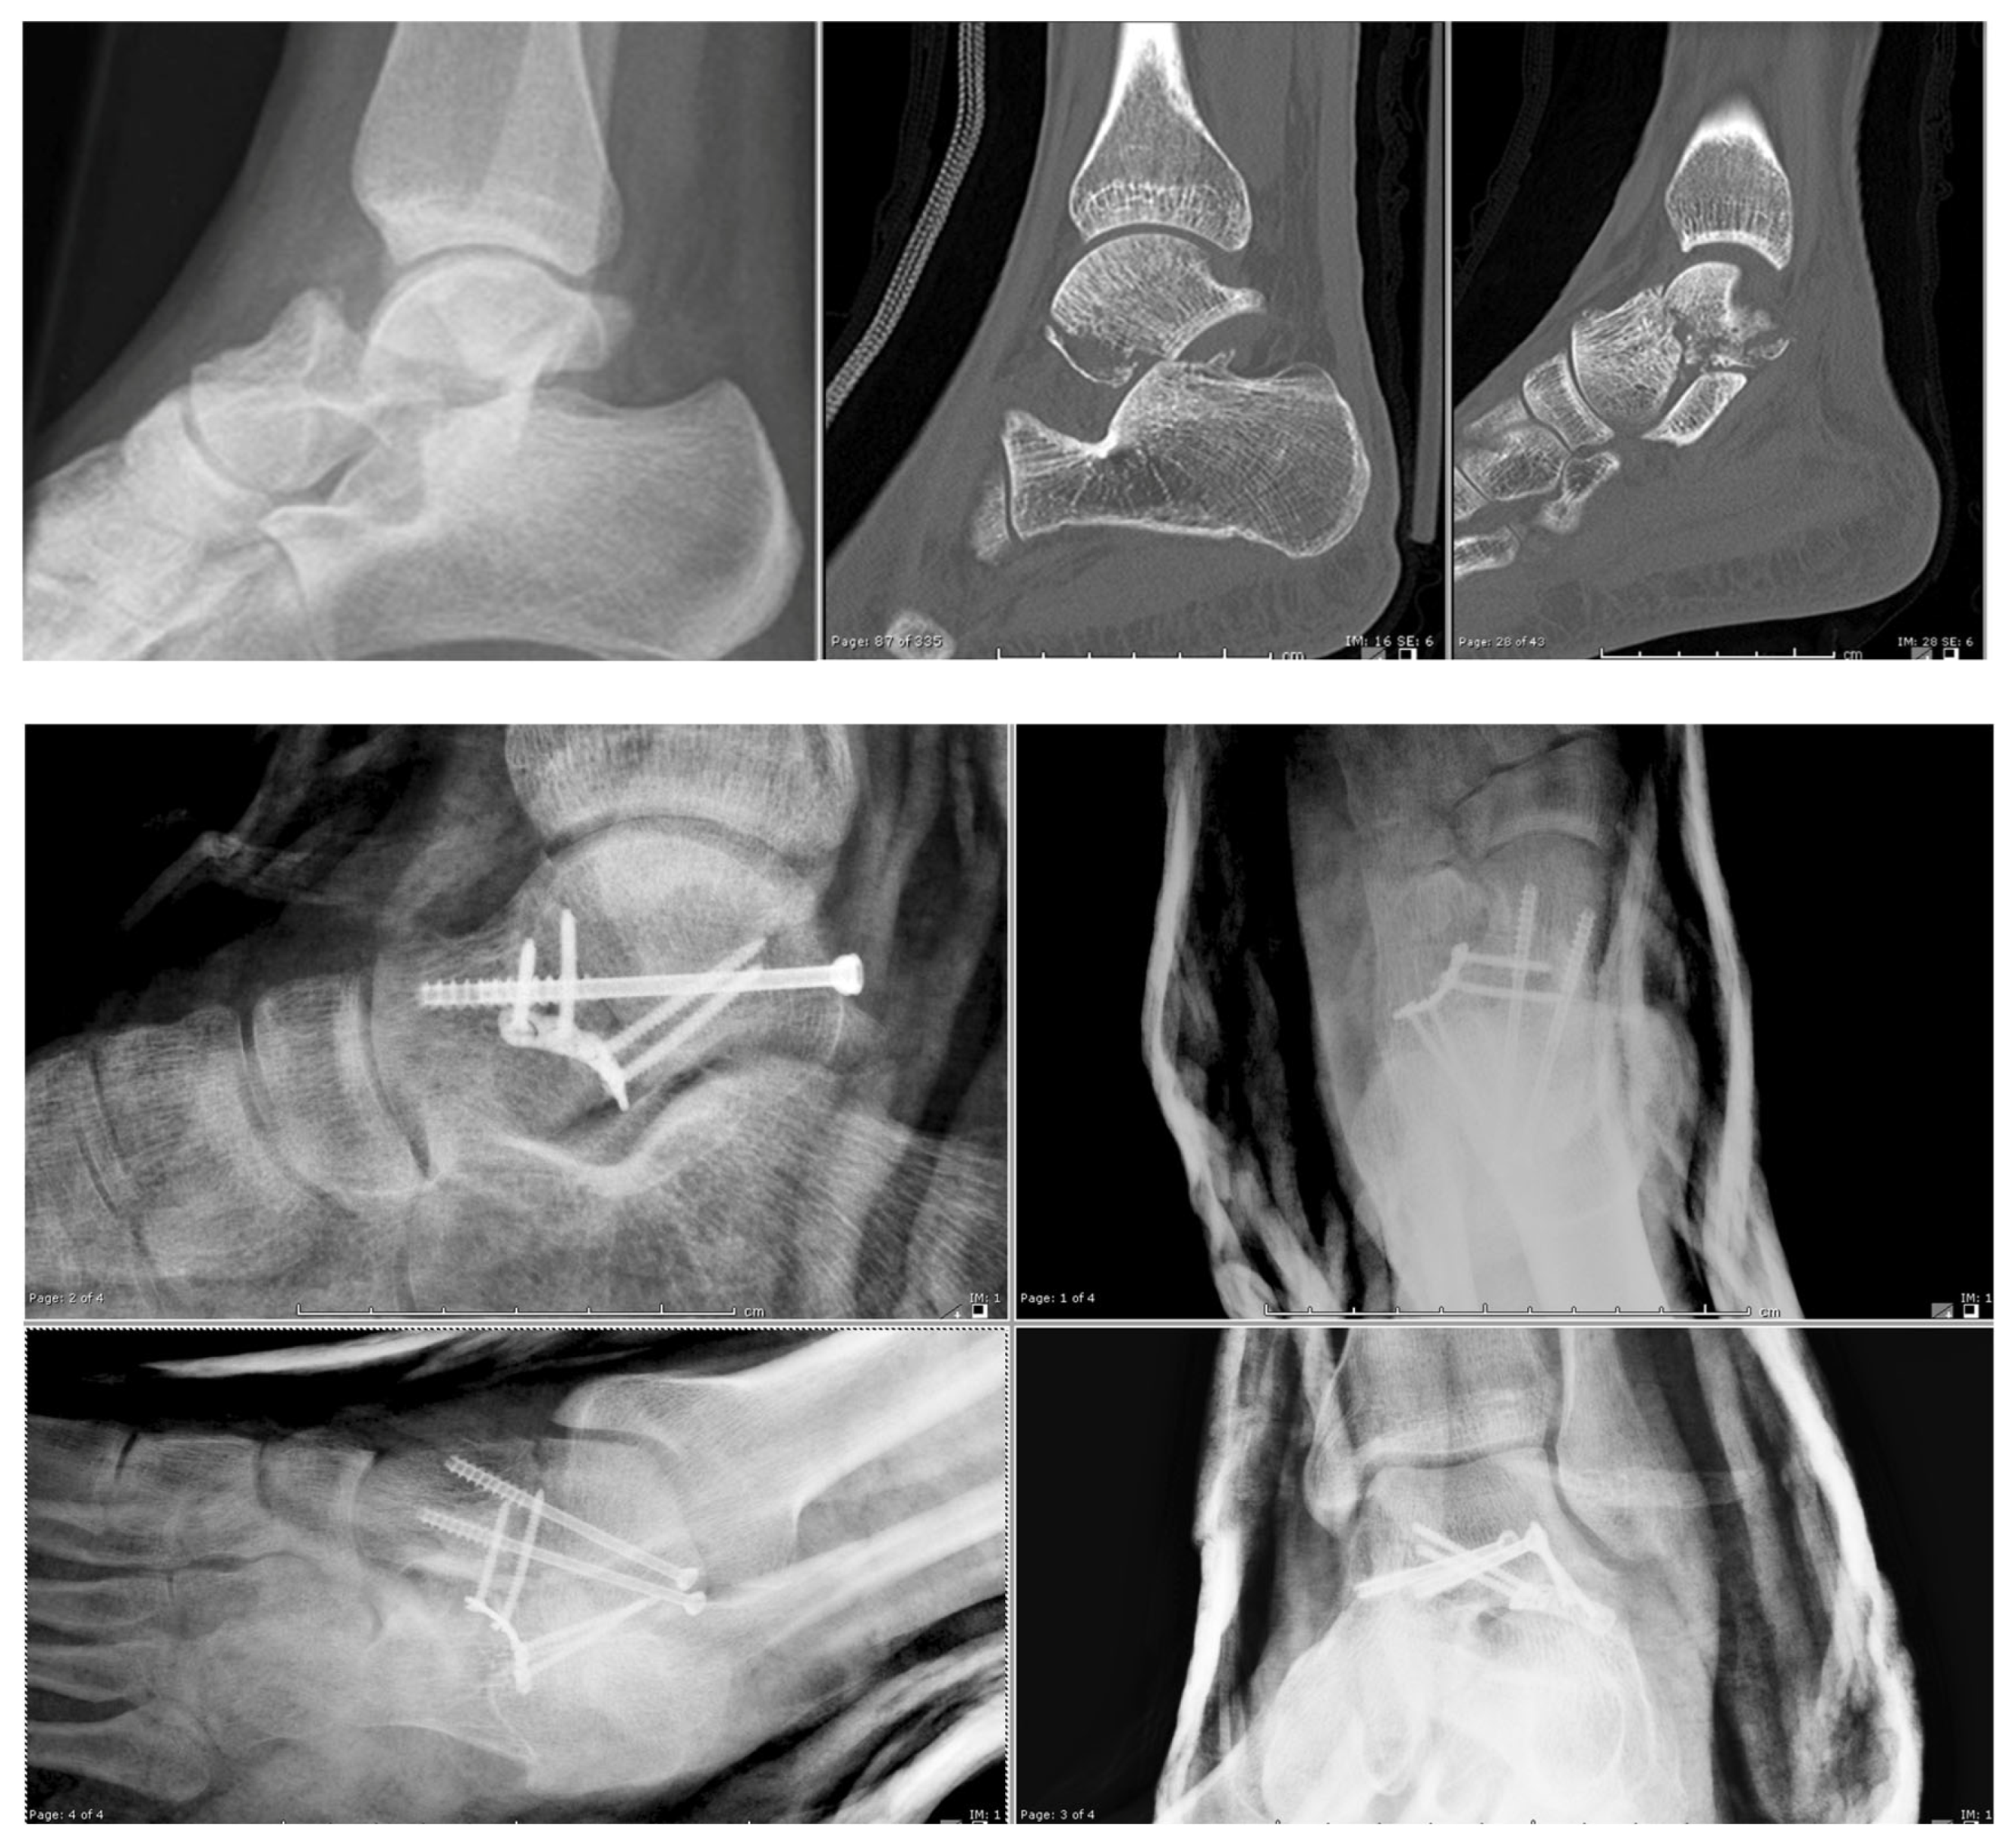

2.1. Surgical Technique